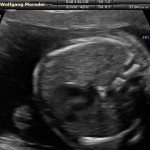

L’ecografia è una tecnica che consente di vedere gli organi del nostro corpo con l’utilizzo di onde sonore ad alta frequenza (ultrasuoni, non udibili dall’orecchio umano) che attraversano i tessuti. La sonda ecografica invia impulsi di onde sonore nel corpo. Quando le onde sonore arrivano al feto mandano degli echi: tali echi (o onde di ritorno) sono trasformati in immagini sul monitor dell’ecografo. Con l’ecografia è quindi possibile osservare in modo dettagliato il feto.

- Perché fare l’ecografia in gravidanza?

Le ragioni più comuni per cui si esegue una ecografia in gravidanza sono: determinare il numero degli embrioni o dei feti, visualizzare l’attività cardiaca fetale, determinare l’epoca di gravidanza, valutare l’anatomia e la crescita fetale, determinare la posizione del feto e della placenta

- Che cosa si vede con l’ecografia?

Nei primi mesi di gravidanza, con la misura della lunghezza del feto, è possibile valutare se lo sviluppo corrisponde all’epoca di gravidanza valutata in base alla data dell’ultima mestruazione, il numero dei feti e la presenza dell’attività cardiaca.

Dal secondo trimestre si misurano altre parti fetali, ed i valori di tali misure vengono confrontati con quelli delle curve di riferimento. Si può così valutare la normalità o meno della crescita fetale. Inoltre periodo si visualizzano la sede di inserzione placentare e la quantità di liquido amniotico.

- E’ possibile rilevare con l’ecografia anomalie fetali maggiori?

La possibilità di rilevare un’anomalia maggiore dipende dalla sua entità, dalla posizione del feto in utero, dalla quantità di liquido amniotico e dallo spessore della parete addominale materna; perciò è possibile che talune anomalie fetali possano non essere rilevate all’esame ecografico. Inoltre alcune malformazioni si manifestano tardivamente (al 7°- 9° mese) e perciò non sono visualizzabili in esami precoci. L’esperienza finora acquisita suggerisce che un esame ecografico routinario, non mirato, consente di identificare dal 30 al 70% delle malformazioni maggiori. Non è compito dell’ecografia la rilevazione delle cosiddette anomalie minori (Linee Guida SIEOG 2006).

- L’ecografia è innocua per il feto?

Gli ultrasuoni sono utilizzati nella pratica ostetrica da oltre 40 anni e non sono stati riportati effetti dannosi, anche a lungo termine, sul feto. Per tale ragione, con le procedure oggi adottate, l’uso diagnostico dell’ecografia è ritenuto esente da rischi. Ovviamente, come in tutte le cose, è bene non eccedere oltre la necessità facendo frequenti esami non necessari.

A fianco alla più tradizionale ecografia eseguita per via transaddominale, risulta particolarmente utile nell’esame ecografico ostetrico e ginecologico la via di accesso transvaginale.

Con questa metodica, utilizzando delle sonde ecografiche appositamente predisposte (per forma e dimensione, e per frequenza di emissione degli ultrasuoni) è possibile controllare la gravidanza nel primo trimestre con una qualità e definizione d’ immagine nettamente superiori a quanto possibile per via transaddominale.

Per eseguire l’ecografia transvaginale non è richiesta la vescica piena, diversamente rispetto a quanto richiesto per l’ecografia transaddominale. L’approccio transvaginale consente di aggirare l’ostacolo dovuto ad un aumentato spessore della parete addominale (obesità). In questi casi infatti la qualità d’ immagine in caso di ecografia transaddominale viene fortemente penalizzata dall’eccessivo spessore del pannicolo adiposo addominale.

Con l’ecografia transvaginale è possibile vedere dopo circa 3 settimane dal concepimento la camera gestazionale nella cavità uterina. Successivamente è possibile visualizzare l’embrione (3-5 mm.) a circa 6 settimane dall’ultima mestruazione (4 settimane dal concepimento) ed a questo periodo è già visibile l’attività cardiaca fetale Anche i primi dettagli sulla morfologia fetale (polo cefalico, abbozzi degli arti) sono visualizzabili più precocemente con l’ecografia transvaginale, risultando essi visibili intorno a 8-9 settimane.

Con l’ecografia dei primi mesi di gravidanza, si può anche valutare la normalità dell’utero (eventuale presenza di fibromi già preesistenti alla gravidanza) e delle ovaie.

Con il finire del primo trimestre per il controllo ecografico di routine della gravidanza la via transvaginale viene poi sostituita dalla via transaddominale.

Successivamente può risultare utile il ricorso all’ ecografia transvaginale nei casi in cui si sospettino delle modificazioni precoci (raccorciamento) del collo dell’utero, come potrebbe verificarsi nei casi di minaccia d’ aborto o di parto pretermine.

In questi casi infatti è possibile con l’ ecografia misurare con precisione la lunghezza del collo uterino. In questi casi inoltre l’ ecografia può anche evidenziare un’ iniziale dilatazione dell’ orifizio uterino interno. Tali modificazioni del collo dell’ utero, valutabili con accuratezza solo con l’ ecografia transvaginale, hanno una grande importanza nel considerare un eventuale rischio di parto pre-termine.